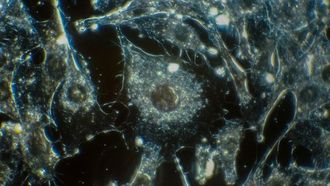

- يعد معهد العلوم البيولوجية في دبي رائداً في تطوير بروتوكولات متقدمة للكشف...

- اكتشف الباحثون في مركز جونسون الشامل للسرطان بجامعة كاليفورنيا في لوس أنج...